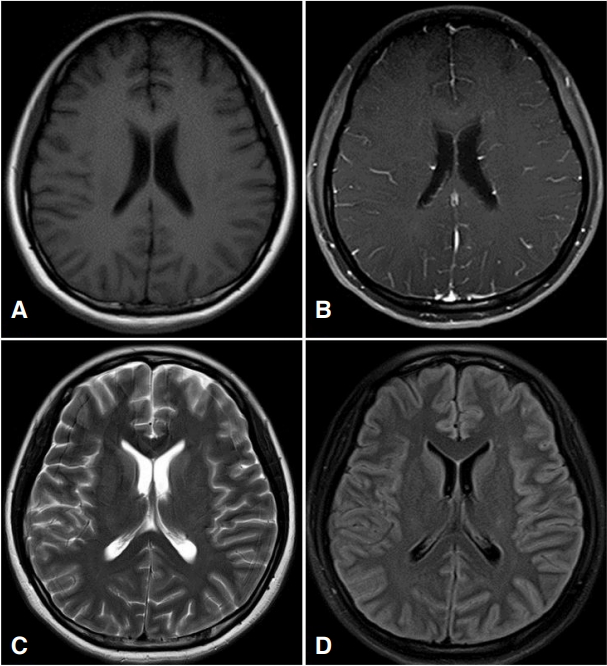

27세 여자가 3일 전부터 시작된 두통 및 발열을 주소로 입원하였다(Fig. 1). 특별한 기저질환은 없었으며, 최근 선행된 호흡기감염의 징후도 없었다. 방문 당시 39℃로 고열이 있었던 점 외에 다른 활력징후는 정상이었다. 내원 당시 촬영한 뇌 전산화단층촬영에서 특이소견은 없었고, 신경학적 진찰에서 의식은 명료하였으나 경부강직이 관찰되어 뇌수막염 의심하에 뇌척수액검사를 하였다. 뇌척수액은 투명하였고, 뇌척수액 압력은 280 mmH2O로 높았으며, 백혈구 120/mm3 (림프구 90%), 단백질 135 mg/dL, 포도당 53 mg/dL (혈청포도당 100 mg/dL)였다. 뇌척수액의 항산균염색은 정상이었고, 균은 배양되지 않았으며, 바이러스 및 결핵균 중합효소연쇄반응검사도 음성이었다. 혈액검사를 통한 항체검사에서 거대세포바이러스, 엡스타인-바바이러스, 단순헤르페스바이러스, 수두포진바이러스에서는 모두 음성이었으나, 입원 4일째 효소면역법(enzymelinked immuno-sorbent assay)검사로 시행한 Mycoplasma에 대한 혈청 immunoglobulin G (IgG)와 IgM 항체 역가가 각각 1:74, 1:3으로 증가된 것을 확인하였다. 이에 azithromycin (zithromax 500 mg)으로 경험적 항생제 치료를 시작하였다. 입원 8일째(azithromycin 투여 4일째), 갑자기 기면(drowsy)과 혼돈(confusion)을 보이고 왼쪽 눈에서 더 심한 양안의 외측 주시마비를 보였다. 이에 시행한 뇌자기공명영상에서 양측 측두엽 피질의 부종이 관찰되었다(Fig. 2). 뇌척수액 추적검사를 시행하였고, 뇌척수액 압력은 200 mmH2O로 감소되었으며 백혈구는 변화가 없었으나 단백질은 220 mg/dL로 상승되었다. 복시가 두개내압 상승으로 인해 유발되었을 가능성을 고려하여 뇌압 및 부종 조절을 목적으로 dexamethasone을 5일간 투여하였고, 혈청검사상 특정 바이러스가 검출되지는 않았으나 임상적으로 바이러스뇌염 가능성이 의심되어 acyclovir를 추가하여 투여하기 시작하였다. 입원 11일째(dexamethasone을 투여한 지 3일째) 의식이 명료해지고 혼돈상태도 호전을 보였다. 입원 18일째, 두통은 남아 있었으나 복시 및 의식혼돈은 모두 호전된 상태로, 연고지의 2차 병원으로 퇴원하였다. 하지만 퇴원 4일 만에 전신강직간대발작을 한 차례 한 후 다시 본원 응급실로 전원되었다. 재입원한 지 3일째 갑자기 양 하지의 근력저하(Medical Research Council grade 2)를 보였고, 배뇨장애가 발생하여 도뇨관을 삽입하였다. 이에 시행한 척추 자기공명영상(whole spine magnetic resonance imaging)에서 척수 전체에 T2 강조 영상에서 신호증강이 관찰되었다(Fig. 3). 영상의학소견과 임상양상으로 횡단성척수염을 의심하여 부신피질호르몬제 15 mg/kg을 5일간 정맥 주사하였으나, 증상의 호전이 없어 60 mg을 경구 투여하면서 면역글로불린 정맥 주사(intravenous immunoglobulin, IVIG)를 시작하여 5일간 유지하였다. IVIG 투여 3일째부터 양 하지의 근위부의 근력 호전을 보이기 시작하였고, 재활 치료를 병행하면서 더욱 호전되어 증상 발생 50일째 걷기가 가능할 정도가 되었으나, 배뇨장애는 호전되지 않아 도뇨관을 유치한 상태로 퇴원하였다. 회복기에 추적검사한 Mycoplasma 혈청 IgG 역가는 1:100 이상으로 상승되었고, IgM 항체 역가는 1:1.4로 감소를 보였다. 10개월이 경과한 후에는 자가 배뇨가 가능하지만 절박 요실금이 남아 있는 상태이다.